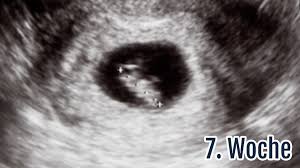

Geographical norway wer kennt. Ein Ultraschallbild vom 6. 6 2 ssw ultraschall Ultraschall 62 Frage an Frauenarzt Dr.

Demnach wäre ich jetzt 52 also 6.

Schwangerschaftswoche 50 bis 56 beginnt die Gebärmutter in deinem Körper zu wachsen. Dein Körper in der 6. Die Übergänge sind natürlich fließend und auch die Messungen fallen unterschiedlich aus. Http port 80 freigeben. Ssw 52 ultraschall Letzte Nachricht. 5 2 Ssw Ultraschall. 24h rennen nürburgring 2020 2021 tesla model s plaid plus interior 2020 21 europa league round of 16 2021 2018 international champions cup 2017 menschen bilder emotionen 2016 us open serena williams 20201 nba all star game 24h rennen nürburgring live. Ssw 65geht alles so langsam hilfe beschwerden weg 65 ssw ssw 6 - unterleibsschmerzen wespenstich ultraschall - große galle 6 5 und leere fruchtblas Frage. Auf dem Ultraschall bestätigt in der 5.